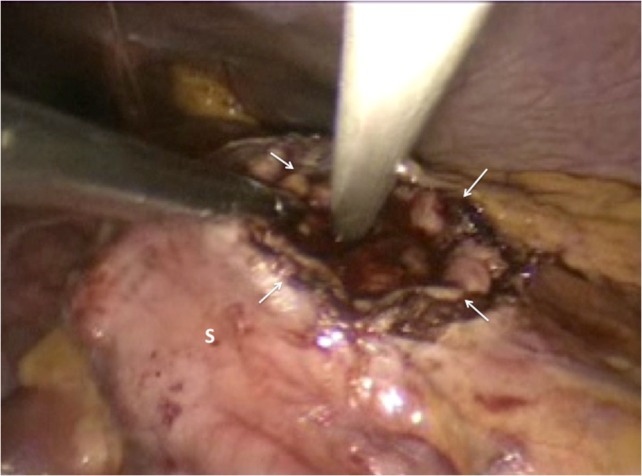

Figure 4:

The gastric lumen was entered through the incision at the anterior stomach wall (margins indicated by white arrows). Conventional straight laparoscopic instrument can be seen developing an tunnel at the posterior stomach wall at the area where bulging from the pseudocyst is most prominent.